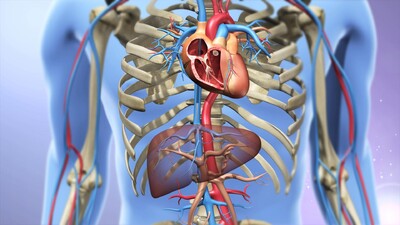

经颈静脉肝内门体静脉分流术(tips)

图片尺寸690x332